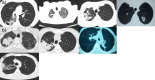

Improved knowledge regarding the tissue penetration of antituberculosis drugs may help optimize drug management. Patients with drug-resistant pulmonary tuberculosis undergoing adjunctive surgery were enrolled. Serial serum samples were collected, and microdialysis was performed using ex vivo lung tissue to measure pyrazinamide concentrations. Among 10 patients, the median pyrazinamide dose was 24.7 mg/kg of body weight. Imaging revealed predominant lung lesions as cavitary (n = 6 patients), mass-like (n = 3 patients), or consolidative (n = 1 patient). On histopathology examination, all tissue samples had necrosis; eight had a pH of ≤5.5. Tissue samples from two patients were positive for Mycobacterium tuberculosis by culture (pH 5.5 and 7.2). All 10 patients had maximal serum pyrazinamide concentrations within the recommended range of 20 to 60 μg/ml. The median lung tissue free pyrazinamide concentration was 20.96 μg/ml. The median tissue-to-serum pyrazinamide concentration ratio was 0.77 (range, 0.54 to 0.93). There was a significant inverse correlation between tissue pyrazinamide concentrations and the amounts of necrosis (R = -0.66, P = 0.04) and acid-fast bacilli (R = -0.75, P = 0.01) identified by histopathology. We found good penetration of pyrazinamide into lung tissue among patients with pulmonary tuberculosis with a variety of radiological lesion types. Our tissue pH results revealed that most lesions had a pH conducive to pyrazinamide activity. The tissue penetration of pyrazinamide highlights its importance in both drug-susceptible and drug-resistant antituberculosis treatment regimens.